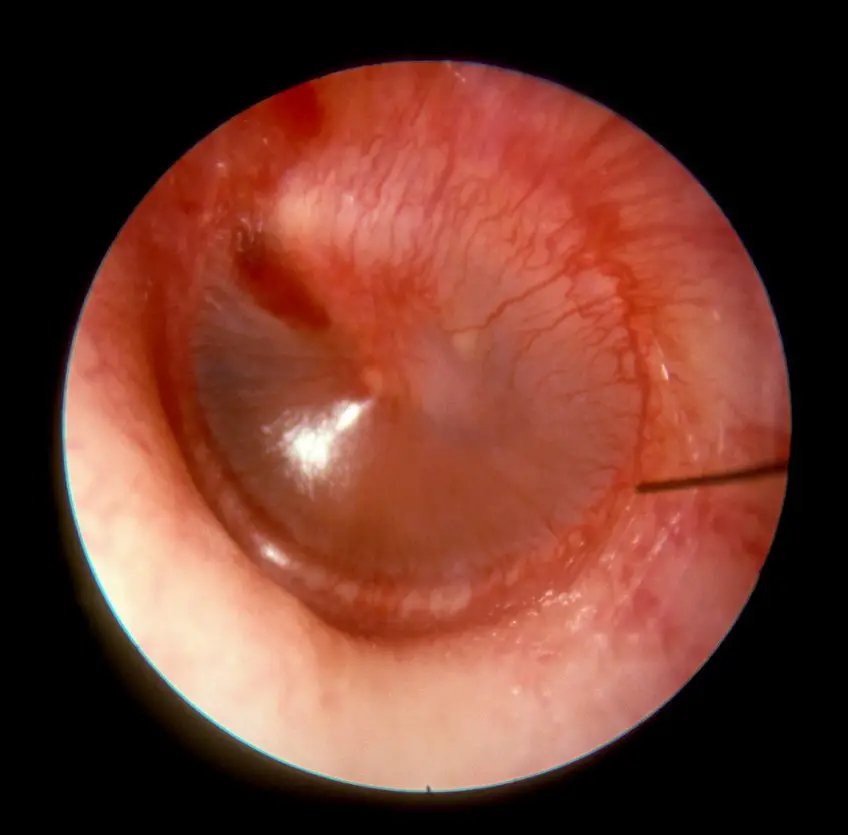

MEDICINA ONLINE OTOSCOPIA IMMAGINE 7 otite

Published 03/09/2018 at 1000 × 985 in Otoscopia del condotto uditivo e del timpano: immagini, funzione

Otite